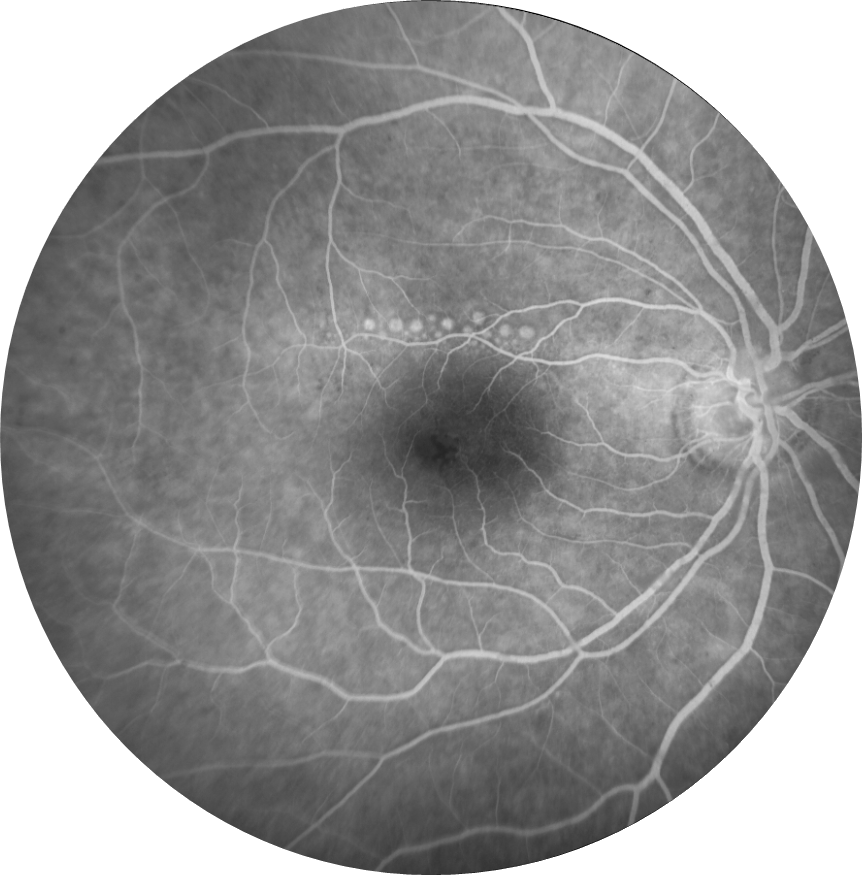

Sağ gözde görme keskinliği 0,3 düzeyinde olan 60 yaşındaki erkek hasta görme azlığı şikayeti ve retina bulguları nedeniyle kliniğimize refere edilmiştir. Hastanın başka bir klinikte 1 yıl önce retina cerrahisi geçirme öyküsü mevcuttur. Hastanın sağ göz renkli fundus, floresein anjiyografi ve optik koherens tomografi görüntülerini görmektesiniz. Bu bulgulara göre tanınız ve resimde fark edilen bulgu nedir? Lütfen cevabınızı aşağıya yazınız.

Bu ay size sağ gözünde görme keskinliği 0,3 düzeyinde olan, 1 yıl önce geçirilmiş retina cerrahisi öyküsü bulunan, 60 yaşındaki erkek hastanın renkli fundus, floresein anjiyografi ve optik koherens tomografi görüntüleri eşliğinde tanısını ve retina bulgusunu sormuştuk.

Tanı: Retina dekolman cerrahisi sonrası retina altında kalmış olan sıvı perflorokarbon (dekalin-Perflorodekalin) damlacıkları’dır.

Retina alt katında hasar çok daha fazla olduğu için burada kimyasal toksisiteden çok mekanik hasar düşünülür. PFK sıvıları jet akımla verildiğinde retina altına gidebilir ve küçük parçacıklar halinde bir bölgede kalabilir. Fovea altına gittiğinde fotoreseptörlere toksiktir ve alınması gereklidir.